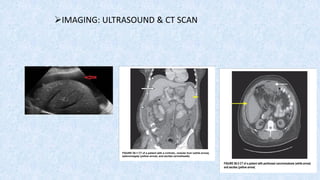

➢IMAGING: ULTRASOUND & CT SCAN